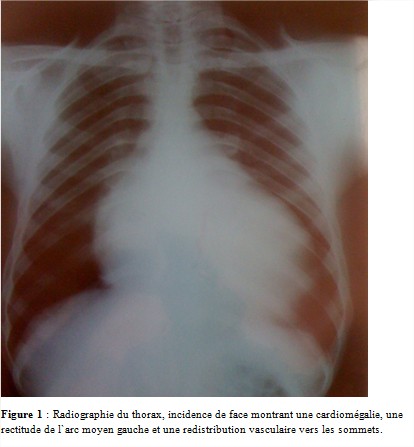

La radiographie du thorax incidence de face (figure 1) montrait une cardiomégalie, une rectitude de l’arc moyen gauche et une redistribution vasculaire vers les sommets.